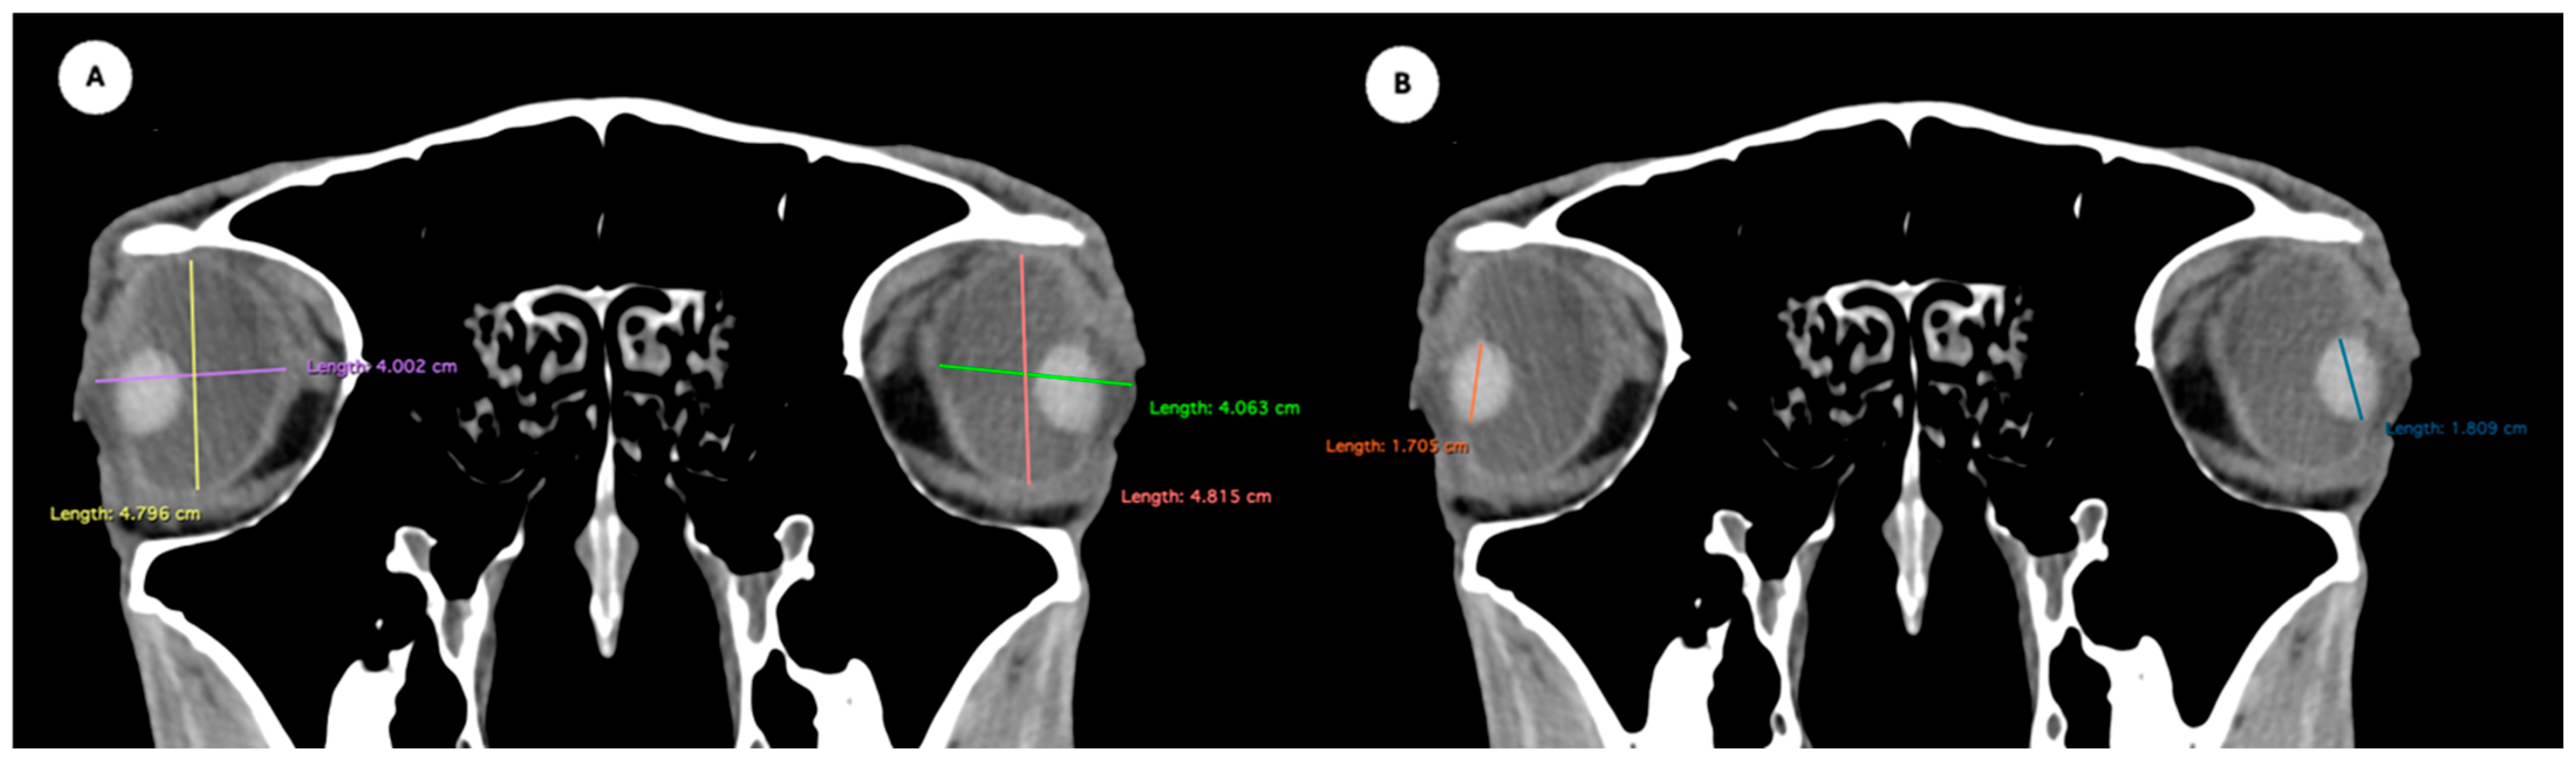

Figure 2. Dorsal multiplanar reconstruction (MPR) images showing (A) the maximal latero-medial distance of the lens and (B) the maximal latero-medial distance of the eyeball, measured perpendicular to the axial length, immediately caudal to the lens. - Orbital cavity height: Maximal dorsoventral distance of the orbital cavity at the level of the eyeball.

- Eyeball equatorial width and height: Maximal anterior–posterior distance (Figure 1A) and maximal lateromedial distance of the eyeball, measured perpendicular to the axial length (Figure 2B).

Table 1 provides summary statistics (mean, median, range, and standard deviation) for the internal ocular measurements of the left eye, right eye, and both eyes combined across all 20 horses. The average ocular measurements indicated that the eyeball height (5.19 ± 0.13 cm) was greater than its width (4.28 ± 0.12 cm), confirming the characteristic oval shape of the equine eye. The mean axial length was 5.09 ± 0.17 cm, consistent with previous descriptions of large-globe morphology in horses. The orbital cavity measured 5.27 ± 0.12 cm in height and 6.29 ± 0.14 cm in length. The anterior and posterior chambers had mean widths of 0.56 ± 0.07 cm and 2.26 ± 0.09 cm, respectively. The lens exhibited a mean height of 1.53 ± 0.06 cm, width of 1.23 ± 0.06 cm, and length of 1.63 ± 0.04 cm. These results collectively reflect the regular proportions and bilateral symmetry of the equine eyeball and its internal structures, as detailed in Table 1. The Mann–Whitney U test revealed no statistically significant differences in the measurements between the right and left eyes. Similarly, when all variables were considered collectively, the analysis confirmed the absence of significant differences between both eyes